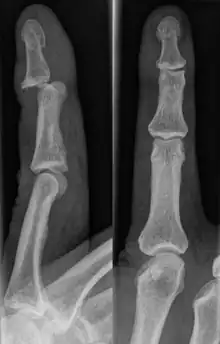

| Jammed ring finger with minor bruising two days after injury | |

| Diagnostic method | Physical Examination and X-rays |

The injured finger may be examined to determine where the pain is worst.[3] If the finger is sprained or dislocated, pain will be worse at the joint rather than the bone.[3] Due to the risk of dislocations or fractures, X-rays should be conducted prior to testing joint stability. This allows for prior detection of a dislocation or fracture.[3] It is recommended that a variety of views (lateral, oblique, and anteroposterior) are observed.[3] In extremely painful cases, a digital nerve block may be done to better assess the finger. This is where anesthetic is injected to either side of the base of the affected finger to reduce pain.[3]

Fractures are instances where the bone's structural integrity has been compromised.[20] If a jammed finger produces a fracture, pain will be greatest at the bone as opposed to the joint.[2] There may also be visual deformation of the bone itself.[6] As with any skeletal injury, an x-ray can be conducted to verify the presence of a fracture.[1] The distal phalanx is especially vulnerable to avulsion fractures.[1] These avulsion fractures are common following a first time dislocation of the DIP.[1]